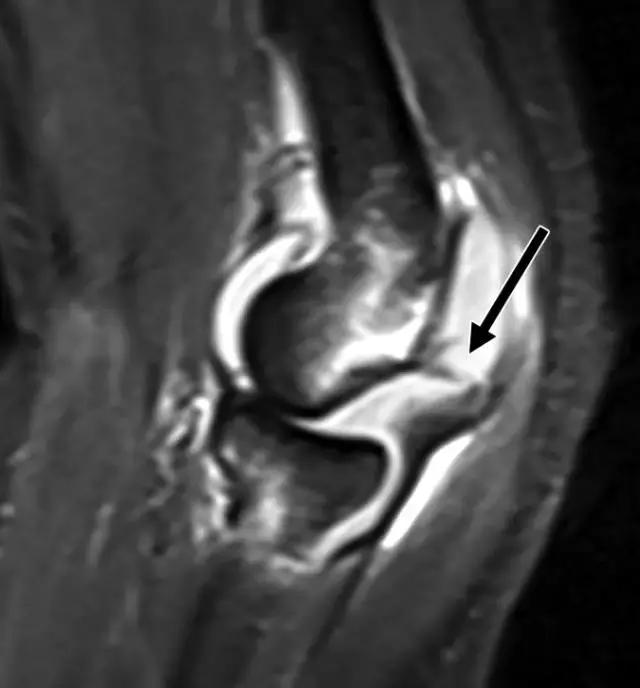

图5A -30岁的Segond骨折患者。A,膝关节前后位X线照片显示沿胫骨外侧平台的薄线状骨折片段(箭头)。

图5B骨折挫伤存在于股骨外侧髁上,前交叉韧带可以看到较低低信号,表明撕裂(箭头)。